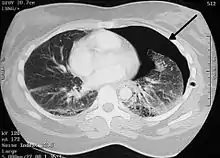

![]() Рентгенівський знімок грудної клітки: у лівій легені прояви пневмотораксу Рентгенівський знімок грудної клітки: у лівій легені прояви пневмотораксу | |

| Метод діагностики | рентгенографія грудної кліткиd, ультразвукове дослідження і КТ |

Коли легеня повністю розправлена, всім пацієнтам необхідно виконати комп'ютерну томографію грудної клітки, що має більшу діагностичну цінність ніж стандартна рентгенографія ОГП. При виявленні бульозних змін у легенях показана відеоторакоскопія з наступним визначенням об'єму операції. Відеоторакоскопію необхідно виконувати також при тривалому (більше 1 тижня) надходженні повітря через дренаж та при рецидивуючому пневмотораксі, особливо якщо рецидив виник протягом року на іпсилатеральній легені.